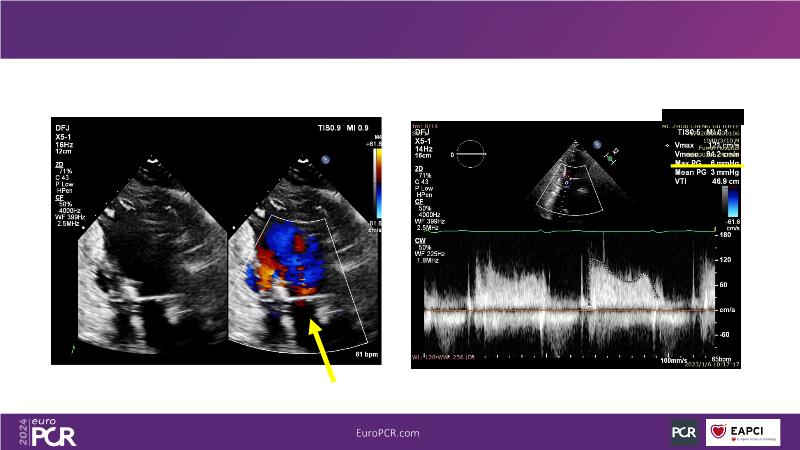

Watch this session to gain insights into the clinical evidence of mitral TEER therapy for the Asian population, learn techniques for implanting a MitraClip in patients with challenging anatomy, and understand how to use the four clip sizes for optimal outcomes. The session also covers educational aspects of clipping in dextrocardia, the benefits of reserve bending of the transseptal needle for tenting and puncture, new steering maneuvers for dextrocardia patients, and the importance of understanding anatomy and collaborating closely with the echo team for success.